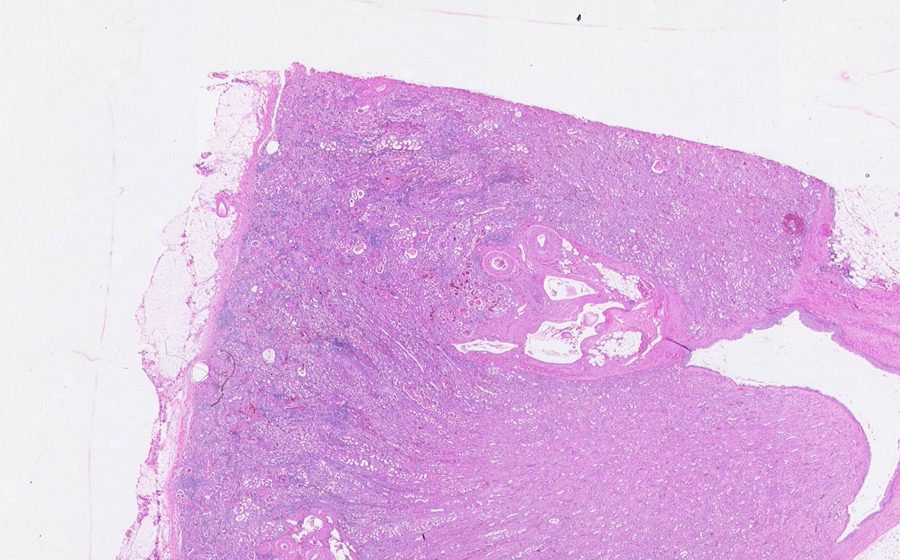

Image 1 - 6.3X

Slide 3 - Image 1